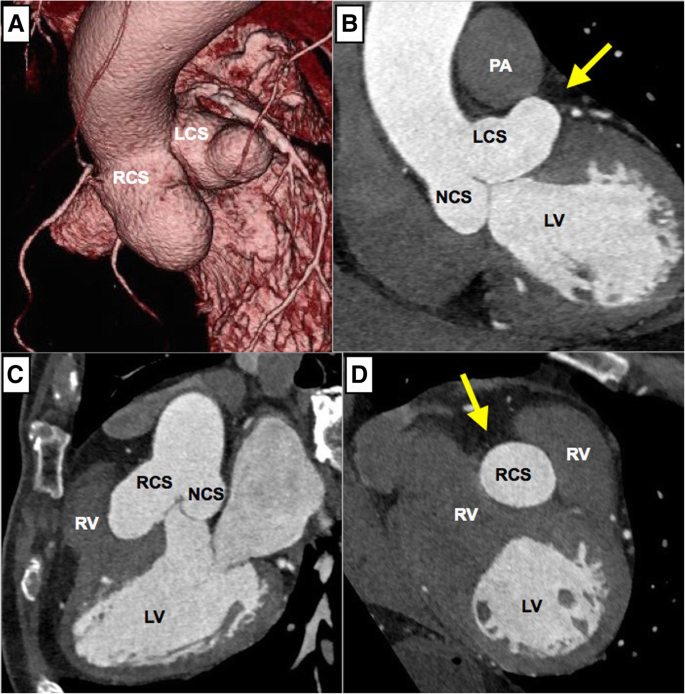

Transthoracic echocardiogram in parasternal shortaxis view shows an aneurysm of left sinus of Valsalva, a mildly dilated noncoronary sinus and a normal right sinus of Valsalva Figure 5) Transesophageal echocardiogram confirms aortic root dilation with an unruptured left sinus of Valsalva aneurysmThe sinuses of Valsalva are dilated cavities between the aortic leaflets and the ascending aortic wall They are subdivided into the left, right and posterior sinuses The sinuses are characterized structurally by their bulging shape protruding into the aortic wall They act as a buffer between the leaflets, giving rise to the left and rightMFS patients with highly dilated (the diameters were equal to or more than 39 mm) SoV (high group, n = 18) and MFS patients